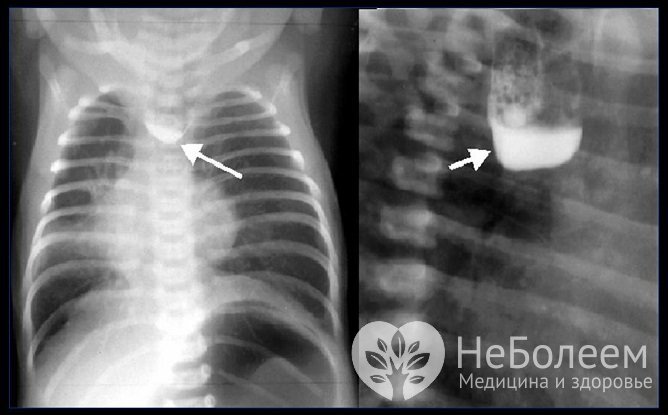

Для установления вида атрезии пищевода выполняют бронхоскопию и эзофагоскопию. Рентгенография с контрастированием бариевой взвесью при данной патологии нередко сопровождается развитием респираторных осложнений, способных стать причиной смерти младенца, поэтому такое исследование выполняют крайне редко и только по строгим показаниям.

Рентгеновский снимок атрезии пищевода у ребенкаАтрезия пищевода требует дифференциальной диагностики со следующими патологиями: